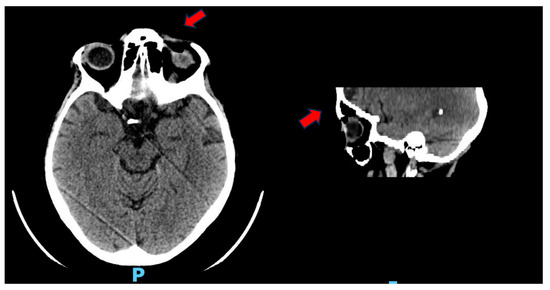

The initial clinical ophthalmological evaluation was followed by an orbital CT, which revealed edematous infiltration of the left periorbital and upper eyelid tissues. An air pocket was also detected at the superior conjunctival fornix, in close contact with the ocular globe (Figure 1). A trial of topical therapy with levofloxacin was initiated, without apparent beneficial effects.

Figure 1. Investigation performed by multilayer spiral technique under baseline and emergency conditions. At the left orbit, minimal edematous suffusion of periorbital and upper eyelid tissue is documented. Concomitant air altitude at the level of the superior conjunctival fornix closely adhered to the surface of the eyeball. Otherwise, no CT evidence of changes of the ipsilateral bulb and retrobulbar soft tissues is documented.